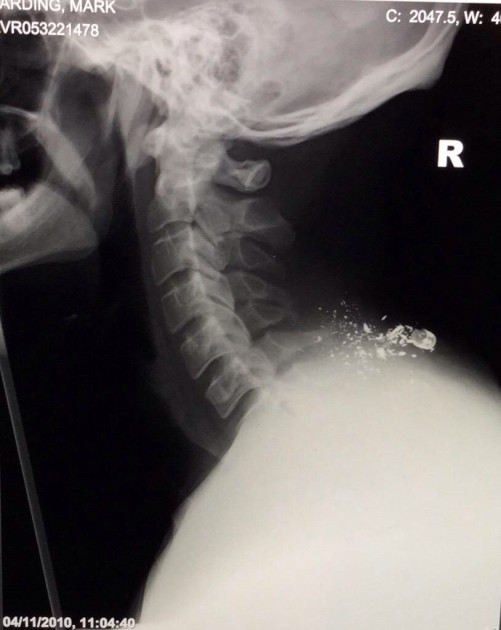

An X-ray showing the bullet shrapnel from Mark's injury

In 2010, while serving in Afghanistan, Mark was shot through the neck. His C5 and C6 spinal segments were completely shattered, resulting in him becoming paralysed from the neck down. Despite being told multiple times that he would never walk again, Mark slowly started to regain some movement, and last year completed a challenge that his doctors would have thought impossible – walking for 85 days across the entire length of the UK.